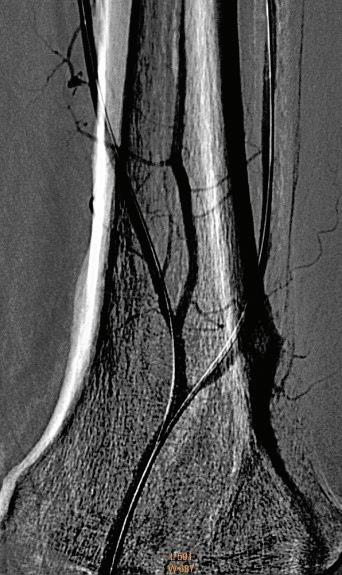

60 КЪСНА РЕВАСКУЛАРИЗАЦИЯ СЛЕД ОСТРА ТРОМБОЗА НА А. СУБКЛАВИА СИНИСТРА –КЛИНИЧЕН СЛУЧАЙ Р. Рунков

62 РЕТРОГРАДНА ПЕРКУТАННА